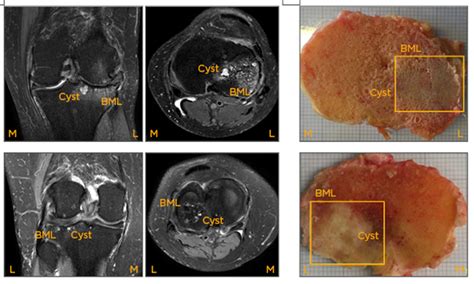

Bone Marrow Degenerative Changes